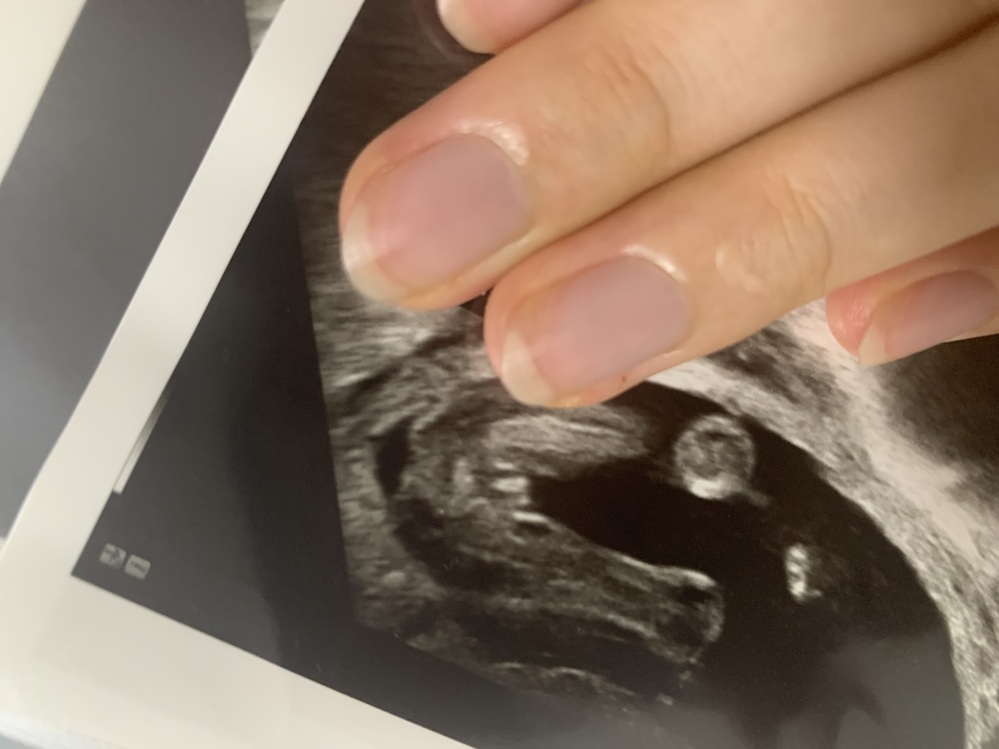

Oct 22, 18 · 最近は、3dエコーや4dエコーが普及して、お腹の中での赤ちゃんの様子をより鮮明にとらえることができるようになりました。 少し費用がかかりますが、3dや4dのエコー検査なら判別の精度があがることがあります。Dec 05, · 赤ちゃんの頭が骨盤にハマるとエコーではどう写るのでしょうか? 👶🏼 先日お腹のエコーしてもらったときに顔がバッチリ見えてあくびとかしてたのですが、見えるということはまだ骨盤にハマってないんですかね?Apr 25, 17 · 骨盤位とは、いわゆる逆子のことで、足やお尻が下にきている状態のことを指します。横位と呼称される場合もありります。 妊婦健診では、お腹の赤ちゃんの成長や健康を確認しますが、同時に赤ちゃんの頭の向き(胎位)も大切な情報になります。妊

Feb 16, 21 · 赤ちゃんが骨盤にはまると胎動が減るといいますが、感じる回数が減るんでしょうか(^_^;)? 胎動の感じが変わるんでしょうか? 胎動自体はちゃんと感じるんですが、今日は最近までの胎動となんとなく 骨盤は小さくはないが差は1センチほどと言われました。次にエコー 第一声‥赤ちゃんMay , 11 · 今日35w2dで健診に行って来たのですが、骨盤に赤ちゃんの頭がはまっていて3Dエコーで赤ちゃんが写らないと言われました。 毎回骨盤が広くて赤ちゃんの頭がはまってるとは言われていたのですが、今回の様にエコーに写らなかったのは初めてです(^_^;)先生はだいぶ下がってきて骨盤に赤ちゃんMar 04, 21 · 医師監修妊娠38週(38w)は、妊娠10ヶ月の3週目です。出産予定日まであと2週間、赤ちゃんが十分に育っている「正期産」という時期になります。お産に向けて子宮口が柔らかくなり、なかには少し開いてくるママも。妊娠38週目の赤ちゃんや、おりものの増加や下痢などママの